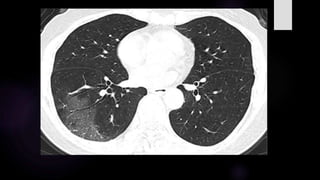

TOMOGRAFIA EN COVID19 SEVERA – CUANTIFICACIÓN DE

SEVERIDAD